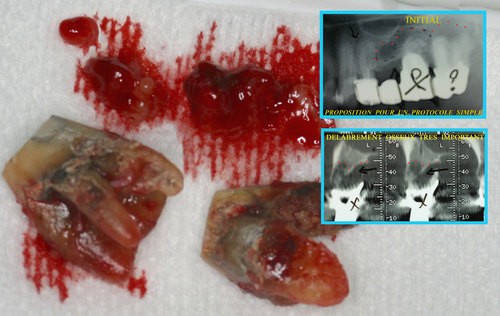

Les infections des dents provoquent des lésions osseuses avec disparition du volume osseux au fur et à mesure que l’infection se propage dans l’os des maxillaires. (fig. 29)

Fig. 29

Les infections dentaires provoquent des pertes osseuses importantes

Cela interdit souvent le port d’une prothèse correcte ou la mise en place d’implants en remplacement des dents absentes.

Un rayonnement laser pénétrant utilisé sous eau oxygénée à 10 volumes permet de décontaminer tout l’os du maxillaire après l’extraction des dents (fig. 30)

Fig. 30

Décontamination du maxillaire après extractions

Cela permet d’envisager immédiatement une régénération osseuse qui est effectuée le jour même des extractions et le résultat à 5 mois postopératoires (fig.31) montre une régénération complète du massif osseux.

Fig. 31

Régénération osseuse du maxillaire